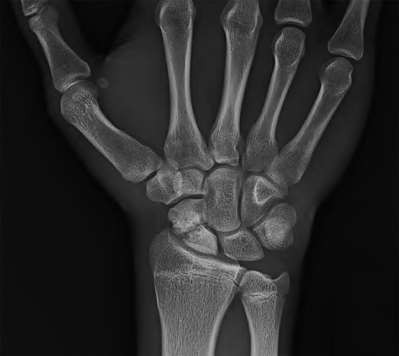

A 35-year-old woman reports wrist pain after a fall onto an outstretched hand. On exam, she has focal tenderness over the wrist snuffbox. A radiograph and CT image are shown in Figures A and B. What is the proper treatment of her injury?